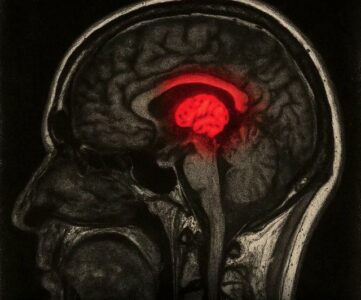

Një studim i ri ka tronditur rrjetet sociale: përdorimi i shpeshtë i TikTok mund të ndryshojë fizikisht trurin e njeriut. Skanimet e trurit kanë treguar se përdoruesit e varur nga TikTok kanë zona të fryra në pjesët që lidhen me shpërblimin dhe emocionet, të ngjashme me ato të të varurve nga kokaina.